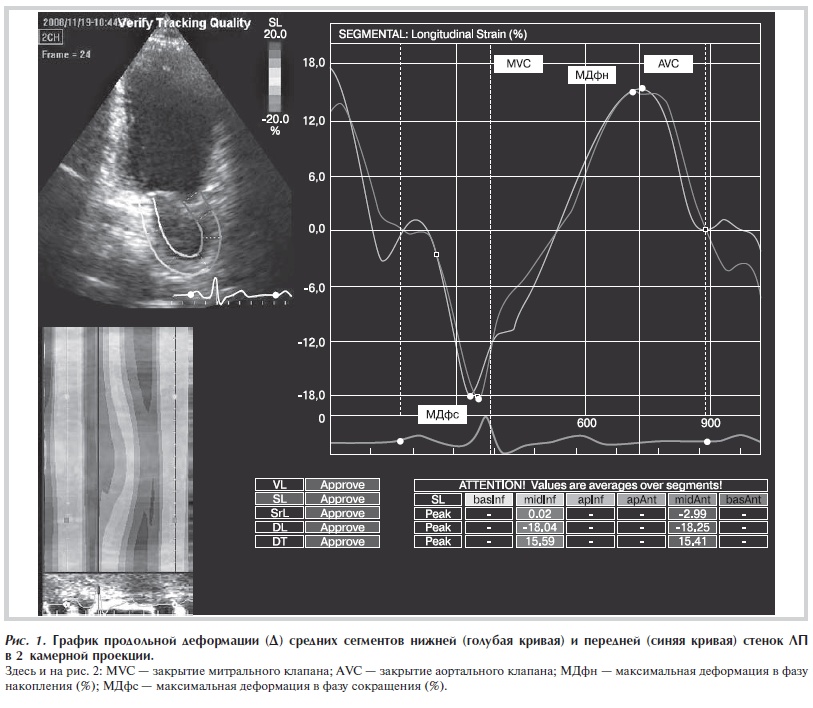

Рисунок 2. График продольной скорости деформации (СД) среднего сегмента задней (голубая кривая) стенки ЛП в 3 камерной проекции.

анализа. В результате анализа программа выстраивает графики продольной деформации и продольной скорости деформации выбранных оператором сегментов предсердия. На рис. 1 и 2 приведены примеры графиков кривых деформации и скорости деформации миокарда ЛП. На полученных графиках проводились измерения деформации и скорости деформации в разные фазы

сердечного цикла. Максимальная продольная деформация была измерена в фазу сокращения (МДфс, %), соответствующую систоле предсердий, от начала зубца Р на ЭКГ до закрытия МК (MVC) и в фазу накопления (МДфн, %), соответствующую систоле желудочков, от закрытия МК до закрытия аортального клапана (AVC). В фазу протекания измерение максимальной деформации не проводилось. Это связано с полученными результатами предыдущей работы, в которой были обследованы здоровые лица [8]. В этом исследовании было продемонстрировано, что в фазу протекания у 50% обследованных здоровых лиц показатели максимальной деформации были равны 0 независимо от сегмента, позиции и качества визуализации. Это связано с отсутствием пика деформации миокарда в указанный период. Деформация в эту фазу переходит из одного пика (максимального удлинения) в другой пик (максимального укорочения) в фазу сокращения. Как известно, в фазу протекания предсердие является пассивным проводником для переноса крови и миокард практически не смещается. Максимальная скорость деформации была измерена в фазу сокращения (МСДфс, 1/s), в фазу накопления (МСДфн, 1/s) и в фазу протекания предсердий (МСДфп, 1/s), соответствующую периоду раннего наполнения ЛЖ с момента открытия МК (MVO) до зубца Р на ЭКГ. МСД и МД рассчитывали для следующих сегментов ЛП: а) в 4-камерной верхушечной позиции для средних сегментов боковой стенки ЛП и ПП, перегородки предсердий; б) в 3-камерной верхушечной позиции для средних сегментов задней стенки ЛП; в) в 2-камерной верхушечной позиции для средних сегментов нижней стенки ЛП и передней стенки ЛП.

Временные интервалы в фазу систолы предсердий были вычислены следующим образом. При анализе

одной из верхушечной позиций (графические кривые деформации и скорости деформации) отмечали 2 точки на ЭКГ в момент начала зубца Р (1-й пункт) и пик зубца R (2-й пункт). Вычисляли разницу между этими пунктами (мс), которая служила постоянной величиной для всех трех позиций (интервал P—R). Затем измеряли разницу времени между 1-м пунктом и пиком волны сокращения ЛП или ПП на графических кривых деформации и скорости деформации (см. рис. 2).